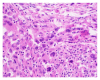

Malignant fibrous histiocytoma (MFH) is one of the most common adult soft tissue sarcomas. MFH is very aggressive and is most often found in the extremities and the retroperitoneum, but it can manifest at other sites. Though the lungs are the most common sites of metastasis, they rarely present there as a primary tumor. Our report describes a rare case of a primary MFH tumor in the lung. Careful diagnostic procedure should be followed to ensure the tumor does not have extrapulmonary origins. Though MFH is highly invasive and deadly, surgical excision of the tumor has been shown to be successful.